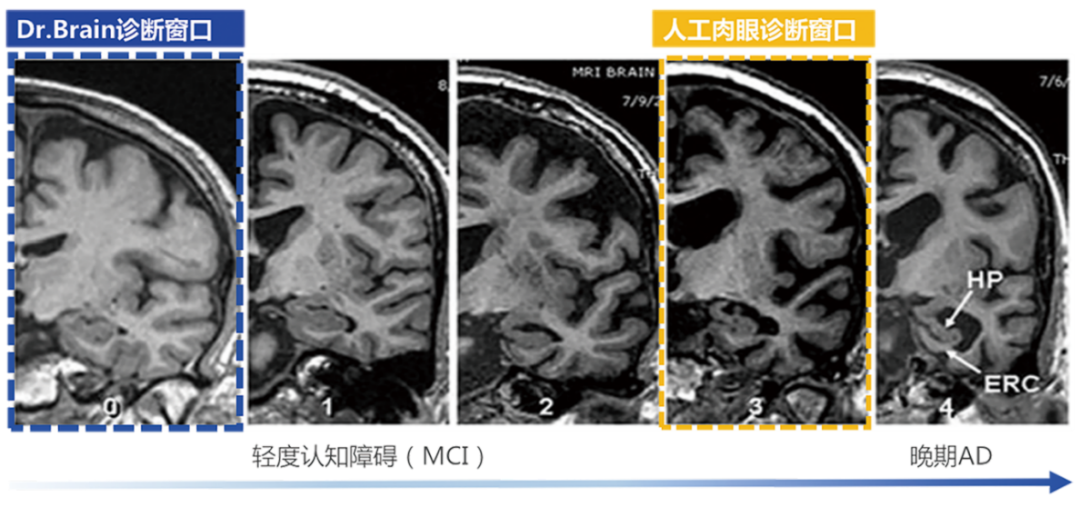

針對(duì)AD的治療,國(guó)際上已批準(zhǔn)的AD藥物基本都是對(duì)早期AD患者在延緩病程發(fā)展上有顯著療效,但對(duì)于晚期患者,即使檢出也是療效甚微?!栋柎暮D?chuàng)新藥物臨床試驗(yàn)中國(guó)專家共識(shí)》強(qiáng)調(diào)AD應(yīng)著力于早期發(fā)現(xiàn)和預(yù)防,而臨床現(xiàn)狀是AD的診斷率低且漏診率高。因此,AD的早篩、早診對(duì)延緩該疾病的發(fā)展至關(guān)重要。臨床中對(duì)AD診斷首選的影像學(xué)檢查方法是磁共振成像 (Magnetic Resonance ImagingMRI) ,但臨床上大多數(shù)醫(yī)生認(rèn)為AD病人的腦結(jié)構(gòu)異常變化發(fā)生較晚,而今借助AI算法,其實(shí)醫(yī)生能在高維空間捕捉到宏觀和微觀、具體和抽象的腦結(jié)構(gòu)特征,可以輔助醫(yī)生利用MRI結(jié)構(gòu)影像在早期精準(zhǔn)診斷AD性質(zhì)的腦結(jié)構(gòu)異常改變。因此,人工智能應(yīng)用于影像診斷和疾病篩查診斷近年來(lái)變?yōu)槿蜥t(yī)療器械業(yè)界的趨勢(shì)與熱點(diǎn),其中,在腦部疾病診療領(lǐng)域,即有可能改變將來(lái)的AD診療路徑。

超早期的診斷

利用AI算法識(shí)別肉眼難以發(fā)現(xiàn)的腦結(jié)構(gòu)超早期的細(xì)微改變,大幅提前疾病診斷窗口